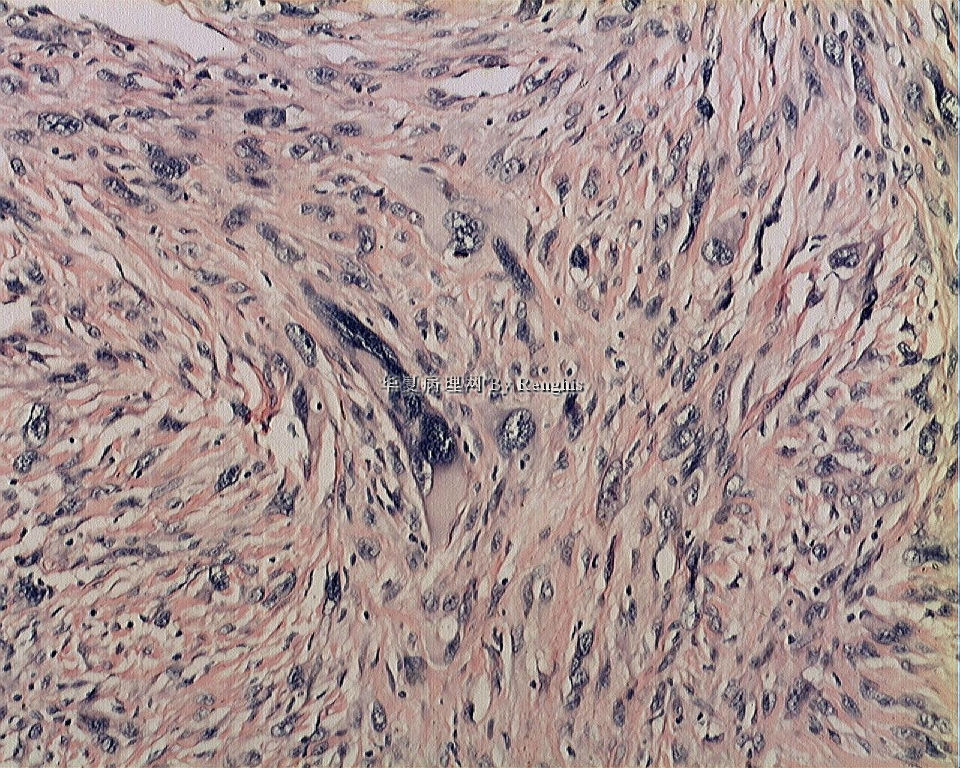

女,29岁,左大腿内侧肿物直径2.8cm,切面灰白、实性、质中,似有包膜。

本例就形态学而言不太符合纤维肉瘤,对于一个多形性和异型明显的肿瘤首先不考虑纤维肉瘤的诊断加上车辐状结构首先还是考虑纤维组织细胞肿瘤。

本人认同此例是一例比较典型的纤维肉瘤,瘤细胞程束状、鱼骨状及编织状排列,部分瘤细胞异型性明显,免疫组化vimentin阳性,SMA灶状弱阳性,desmin阴性,S100阴性,CK阴性,EMA阴性,余记不得了,明天看看再上传。